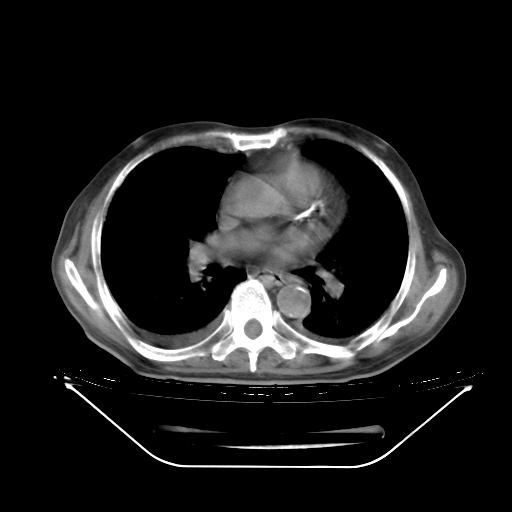

今天复查肺部CT,发现双肺广泛磨玻璃样改变。所以我把3月19日和5月9日相隔50天的肺部CT上传。请大家会诊。

2009年3月19日肺部CT片。

5月9日肺部CT(在4月27日齐鲁医院肺部CT描述部分肺组织磨玻璃样改变,12天后肺组织广泛磨玻璃样改变)